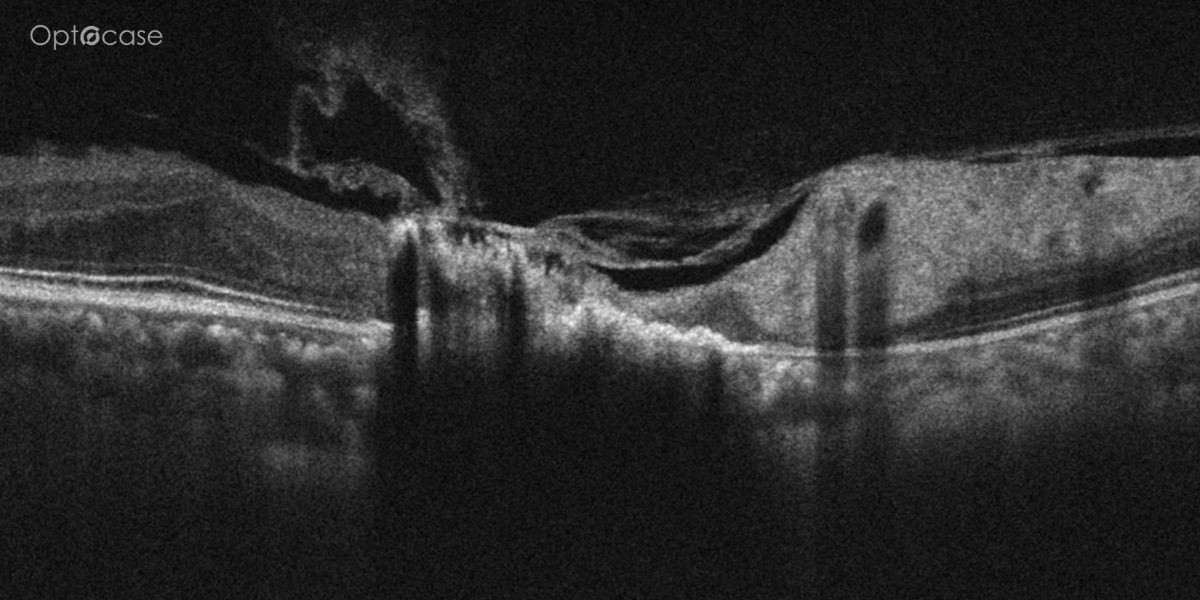

A 73-year-old presents with new distortion. Why?

Here there is loss of the regular macular depression. There is a bright line present on the surface of the retina. In addition, there is separation of the retinal layers in the inner retina.

The patient was diagnosed with a schisis secondary to an epiretinal membrane. This complication is seen in over 50% of ERMs (video).